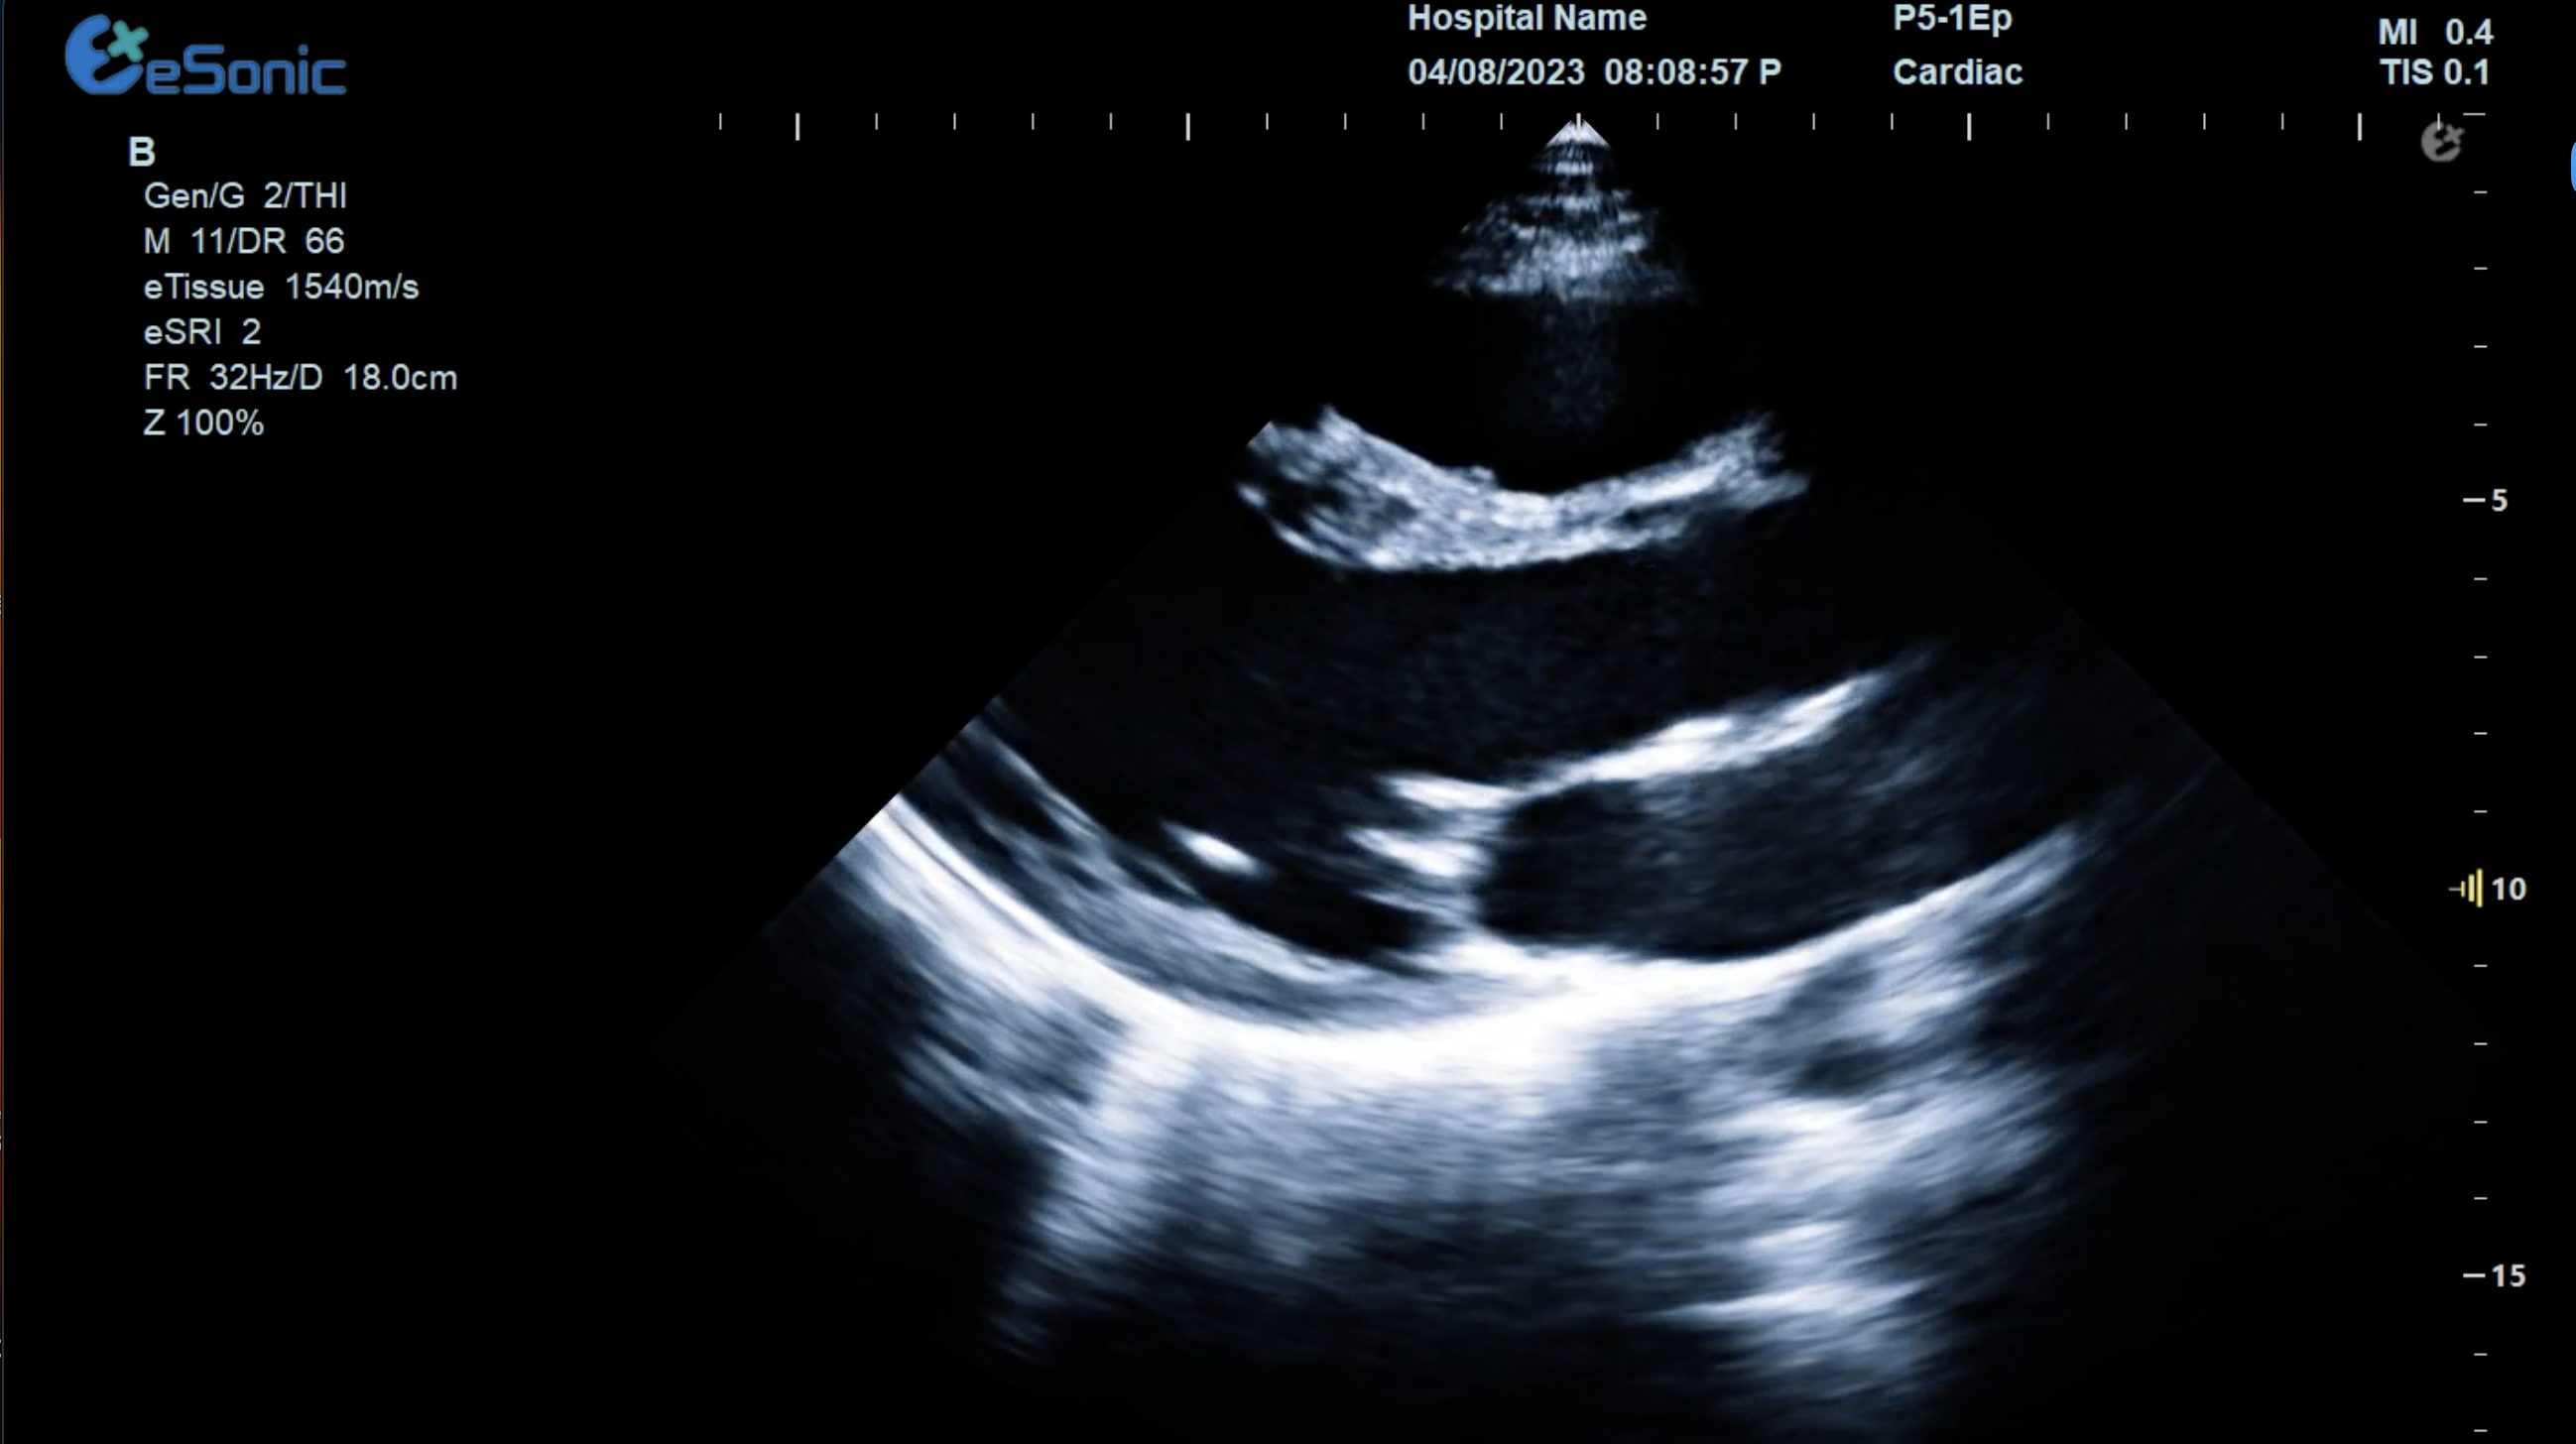

图像清晰?:提供高分辨率、高穿透优异图像,满足急重症卧床病患诊疗,帮助临床医生清晰地看到病灶。急重症.jpg

急重症超声心动图用于心脏病诊断的适应症

先心病:ASD、VSD、 F4 、AS、PS等;心内膜垫缺损、大动脉转位、左/右心发育不良等。瓣膜病:风心病、老年退化性心脏病.  SIE。心包疾病:积液(PE)、肿瘤、填塞等。

心肌疾病:扩张型、肥厚型、限制型和特发型等。大血管疾病:主动脉夹层、缩窄、动脉瘤等。冠状动脉疾病:冠心病、川崎病、畸形。其他:外伤、异物等

临床病例(一)

女性,68岁,临床诊断:冠心病

超声表现:左房大,左室壁运动幅度明显减低,以室间隔较明显;心包腔内见无回声区,右室前壁8mm,左室侧壁10mm。

冠心病、心包积液